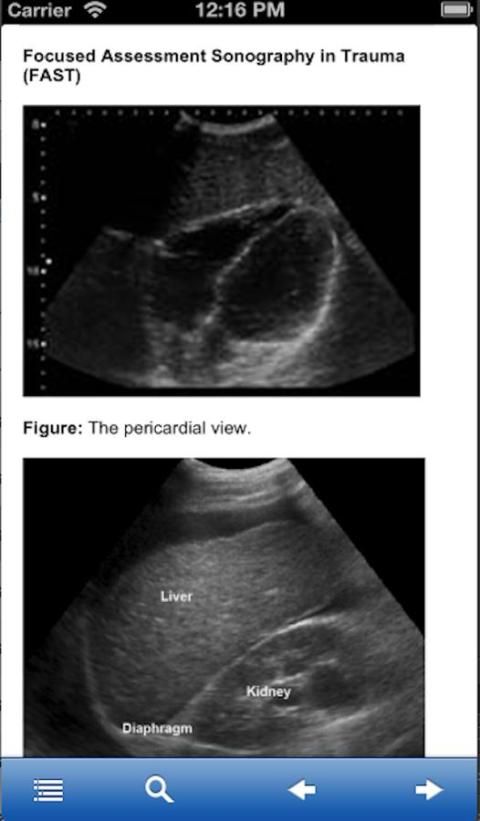

Основное внимание оценке Сонография Травма

Пожалуйста, ознакомьтесь с изображения на экране перед загрузкой.